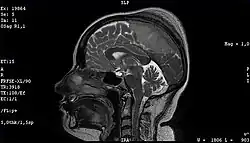

Imaging

Medical imaging plays a central role in the diagnosis of brain tumors. Early imaging methods – invasive and sometimes dangerous – such as pneumoencephalography and cerebral angiography have been replaced by non-invasive, high-resolution techniques, especially magnetic resonance imaging (MRI) and computed tomography (CT) scans.[42] MRI with contrast enhancement is the preferred imaging test in the diagnosis of brain tumors.[24][43] Glioblastomas usually enhance with contrast on T1 MRI weighted MRI imaging, and on T2 with FLAIR imaging showing hyperintense cerebral edema.[24] Low grade gliomas are usually hypointense on T1 MRI, and hyperintense with T2 with FLAIR MRI. Meningiomas are usually homogenously enhanced with dural thickening on MRI.[24]